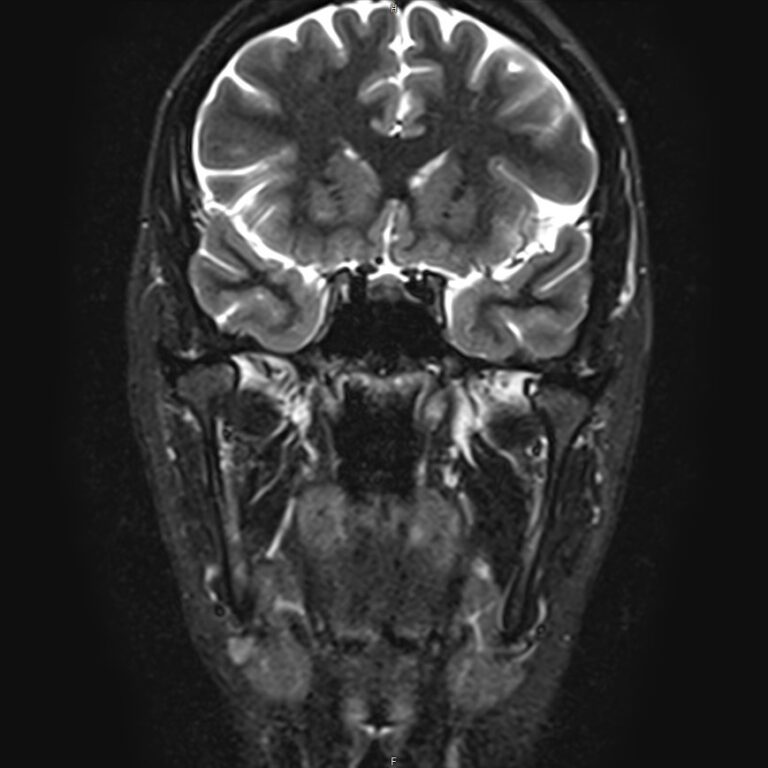

Височно-нижнечелюстной сустав является парным комбинированным суставом и имеет сложное строение. В него входят суставные ямки височной кости, суставные головки нижней челюсти и расположенные между ними хрящевые пластинки – мениски, выполняющие роль амортизаторов.

Чаще всего дисфункция височно-нижнечелюстного сустава обусловлена внутренним повреждением, смещением мениска и суставной головки нижней челюсти. Для определения степени смещения внутрисуставных структур выполняется функциональная проба с проведением МРТ в двух положениях:

• с закрытым ртом;

• с открытым ртом.

Магнитно-резонансная томография является наиболее точным и эффективным методом диагностики поражения височно-нижнечелюстных суставов, так как позволяет получить детальную информацию о состоянии не только костей, но и связочного аппарата, хрящей, менисков, жевательных мышц, окружающих мягких тканей.

При проведении магнитно-резонансной томографии на изображениях визуализируются: височная кость, головка мыщелкового отростка нижней челюсти, суставная щель. Помимо костных структур МРТ позволяет оценить состояние мягких тканей – внутрисуставного диска и связочного аппарата височно-нижнечелюстного сустава, жевательных мышц.